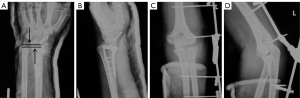

All cases were evaluated by X-ray and computed tomography (CT) examinations on the wrist and elbow joints before operation (Figures 1,2). Fractures classifications of the 13 patients are shown in Table 1. The radial head fractures were categorized based on the Mason classification, including 1 case of type I, 7 cases of type II, and 2 cases of type III. There were 2 cases that were combined with radial neck fractures.

Patients were given postoperative protective braces for no more than 1 week. The elbow extension was limited not exceed 30° within 1 month (Figure 3). If the gravity stability test showed that the joint was still unstable after confirming the reduction of the elbow joint, fracture fixation, and ligament repair, the joint could be fixed with the elbow hinge fixator for no more than 1 week.